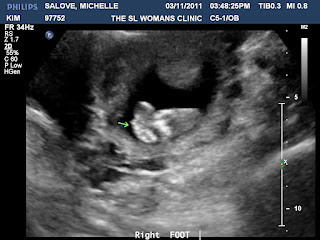

Sweet little piggies...